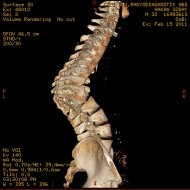

Omurga veremi sonucu kifoz oluşan hastanın ameliyat öncesi ve sonrası filmleri: